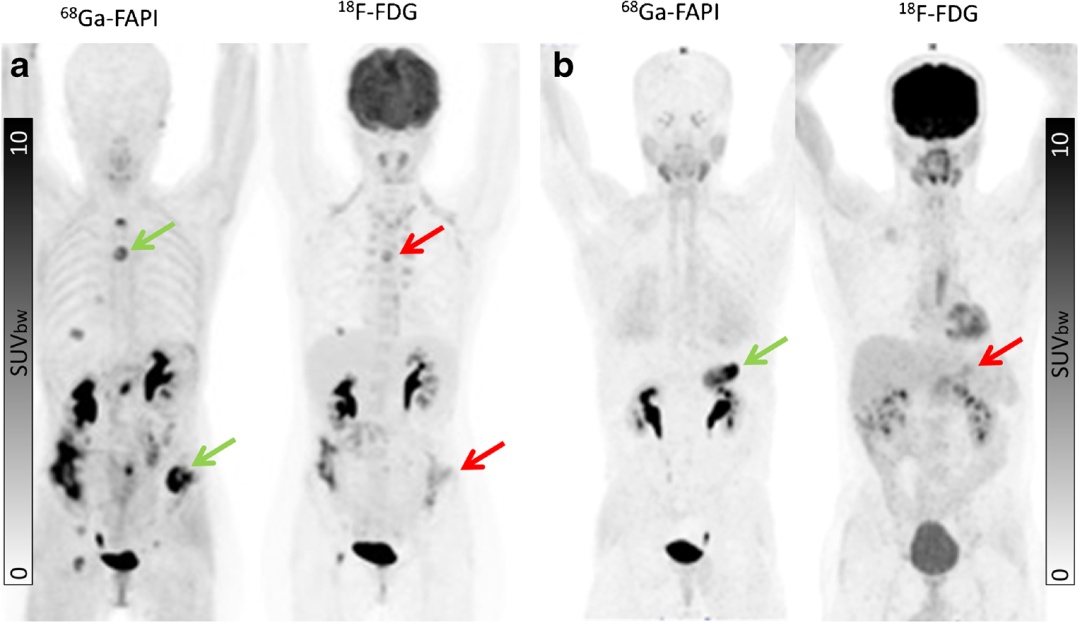

2019年核医学领域著名的年度图像:68Ga-FAPI PET/CT多种类型肿瘤显像图(图1)就展示出其强大的优势,显示了FAPI在12种主要癌症类型中的摄取。

图1 SNMMI 2019年度图像:68Ga-FAPI-PET/CT应用于12种不同类型肿瘤患者的显像结果

原发灶和转移灶的探查中,FAPI在胃癌、结直肠癌、食管癌、乳腺癌、胰腺癌、肝胆系统肿瘤、肺癌、头颈部鳞癌、卵巢癌等多种上皮来源肿瘤及其转移灶具有较高的敏感性。腹膜种植转移、胸膜肿瘤及胸膜的侵犯上,FAPI PET也显出优于FDG的检出能力。骨转移,尤其是成骨性或混合性骨转移,FAPI同样能更早、更清晰地显示病灶(图2)。

图2 卵巢癌(a)和胰腺癌(b)两位患者分别行FDG和FAPI PET显像。相较于FDG(红色箭头),两位患者表现出更为显著的FAPI摄取(绿色箭头),反映出良好的靶/非靶比值[2]